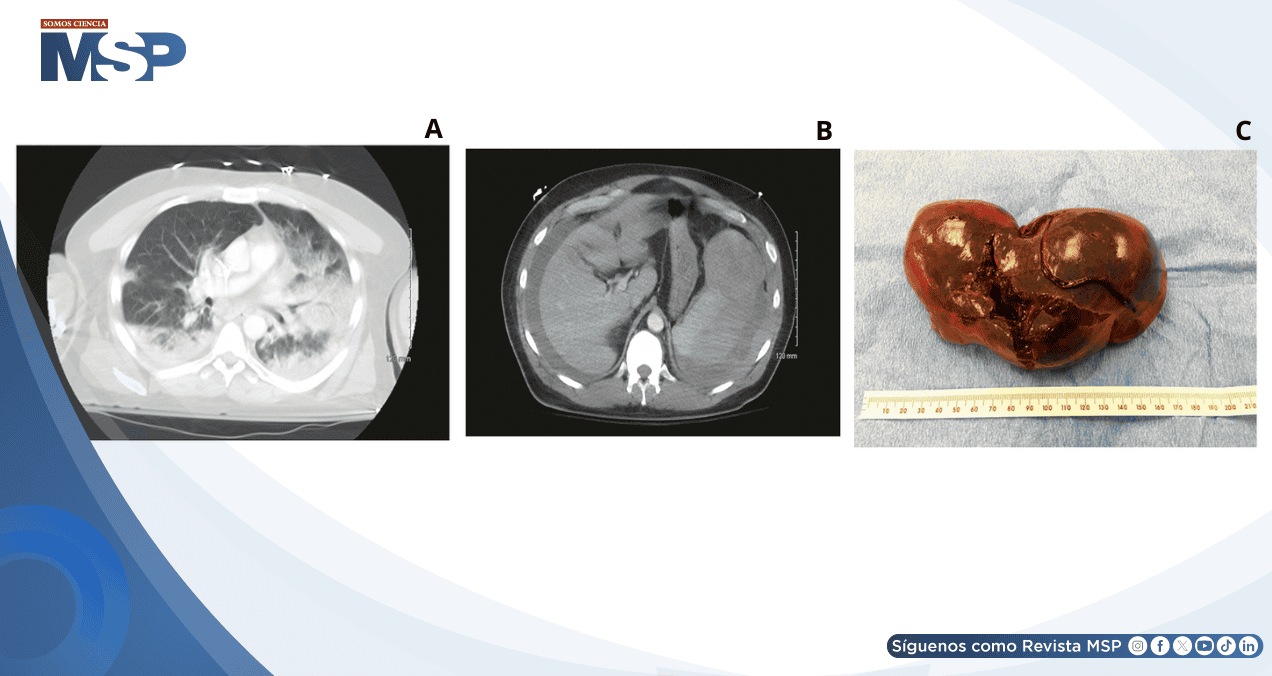

La tomografía computarizada reveló consolidación pulmonar extensa sin embolia pulmonar, y hallazgos abdominales alarmantes: líquido perihepático y perisplénico con margen esplénico indistinto y áreas de baja densidad sugestivas de lesión o ruptura esplénica. Llamativamente, el paciente negó cualquier antecedente traumático.

Ante la sospecha de hemorragia activa y valores de hemoglobina decrecientes a pesar de transfusiones, se realizó embolización de arteria esplénica sin éxito. La hemoglobina continuó descendiendo (7.7 g/dL) pese a recibir 3 unidades de concentrado eritrocitario, por lo que se procedió a laparotomía de emergencia con esplenectomía.

Los hallazgos intraoperatorios confirmaron hemoperitoneo extenso con bazo hemorrágico presentando una laceración de 10 cm que prácticamente bisecaba el órgano.

El estudio anatomopatológico describió un bazo de 521 gramos con superficie capsular intensamente hemorrágica, laceración irregular extensa y un pequeño hemangioma de 1.5 cm sin evidencia de sangrado activo ni malignidad.